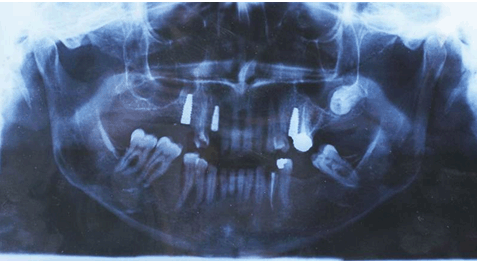

Panoramic radiograph revealed the presence of three implants restoring lost maxillary right second premolar, maxillary left canine and maxillary left second premolar (Figure 2).

Figure 2: Preoperative panoramic radiograph showing inserted implants.